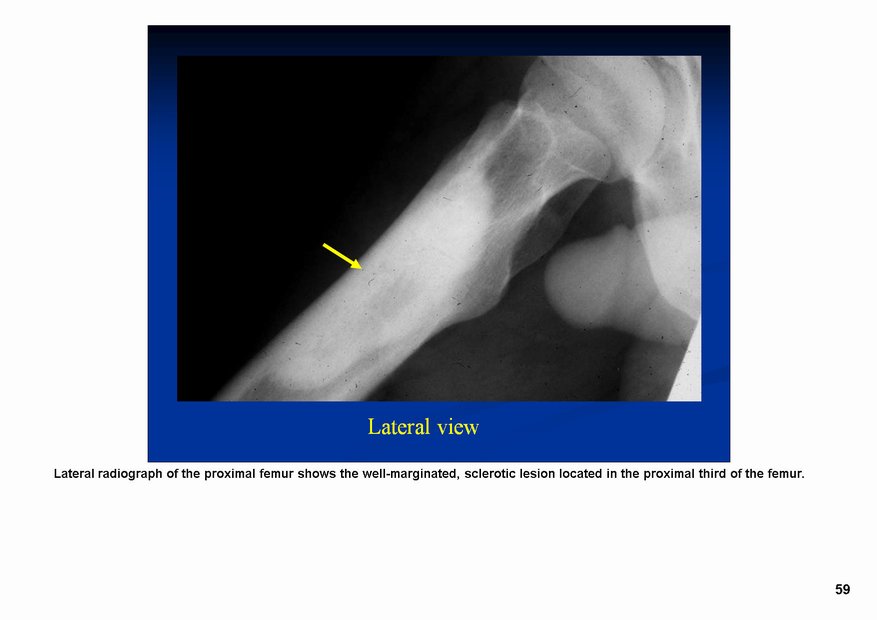

Фиброзная дисплазия — заболевание, характеризующееся нарушением развития (дисплазия) скелета, при котором нормальная кость замещается фиброзной тканью с элементами диспластически изменённой кости. Выделяют монооссальную (около 85% случаев), мономелическую (поражено несколько соседних костей одной конечности, плечевого или тазового пояса) и полиоссальную (около 5% случаев) формы. Фиброзная дисплазия как аномалия развития иногда сочетается с внескелетными расстройствами: 1) полиоссальная форма поражения сочетается с преждевременным половым созреванием и пигментными пятнами на коже в виде кофейных пятен (Albright’s syndrome); 2) сочетание фиброзной дисплазии с миксомами мягких тканей (Mazabraud’s syndrome). Встречается в любом возрасте, наиболее часто в первые 3 десятилетия жизни (70% больных). Монооссальная форма несколько чаще встречается у лиц мужского пола, при полиоссальной форме соотношение лиц мужского и женского пола 2 : 1. Поражается любая кость, наиболее частая локализация: проксимальная часть бедренной кости, большеберцовая и плечевая кости, рёбра, кости черепа, шейного отдела позвоночника. Поражение костей позвоночника только в 2,5% случаев.